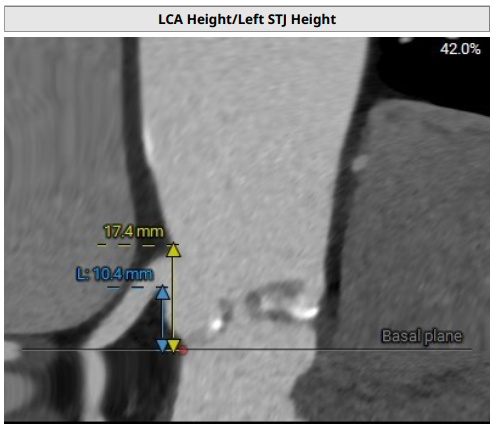

法式窦空间小;STJ高度17.4mm,均径26.4mm;升主动脉40mm处均径36.1mm;心脏角度52°;

LCA:10.4mm;RCA:13.2mm;窦部空间小,右冠风险不排除;